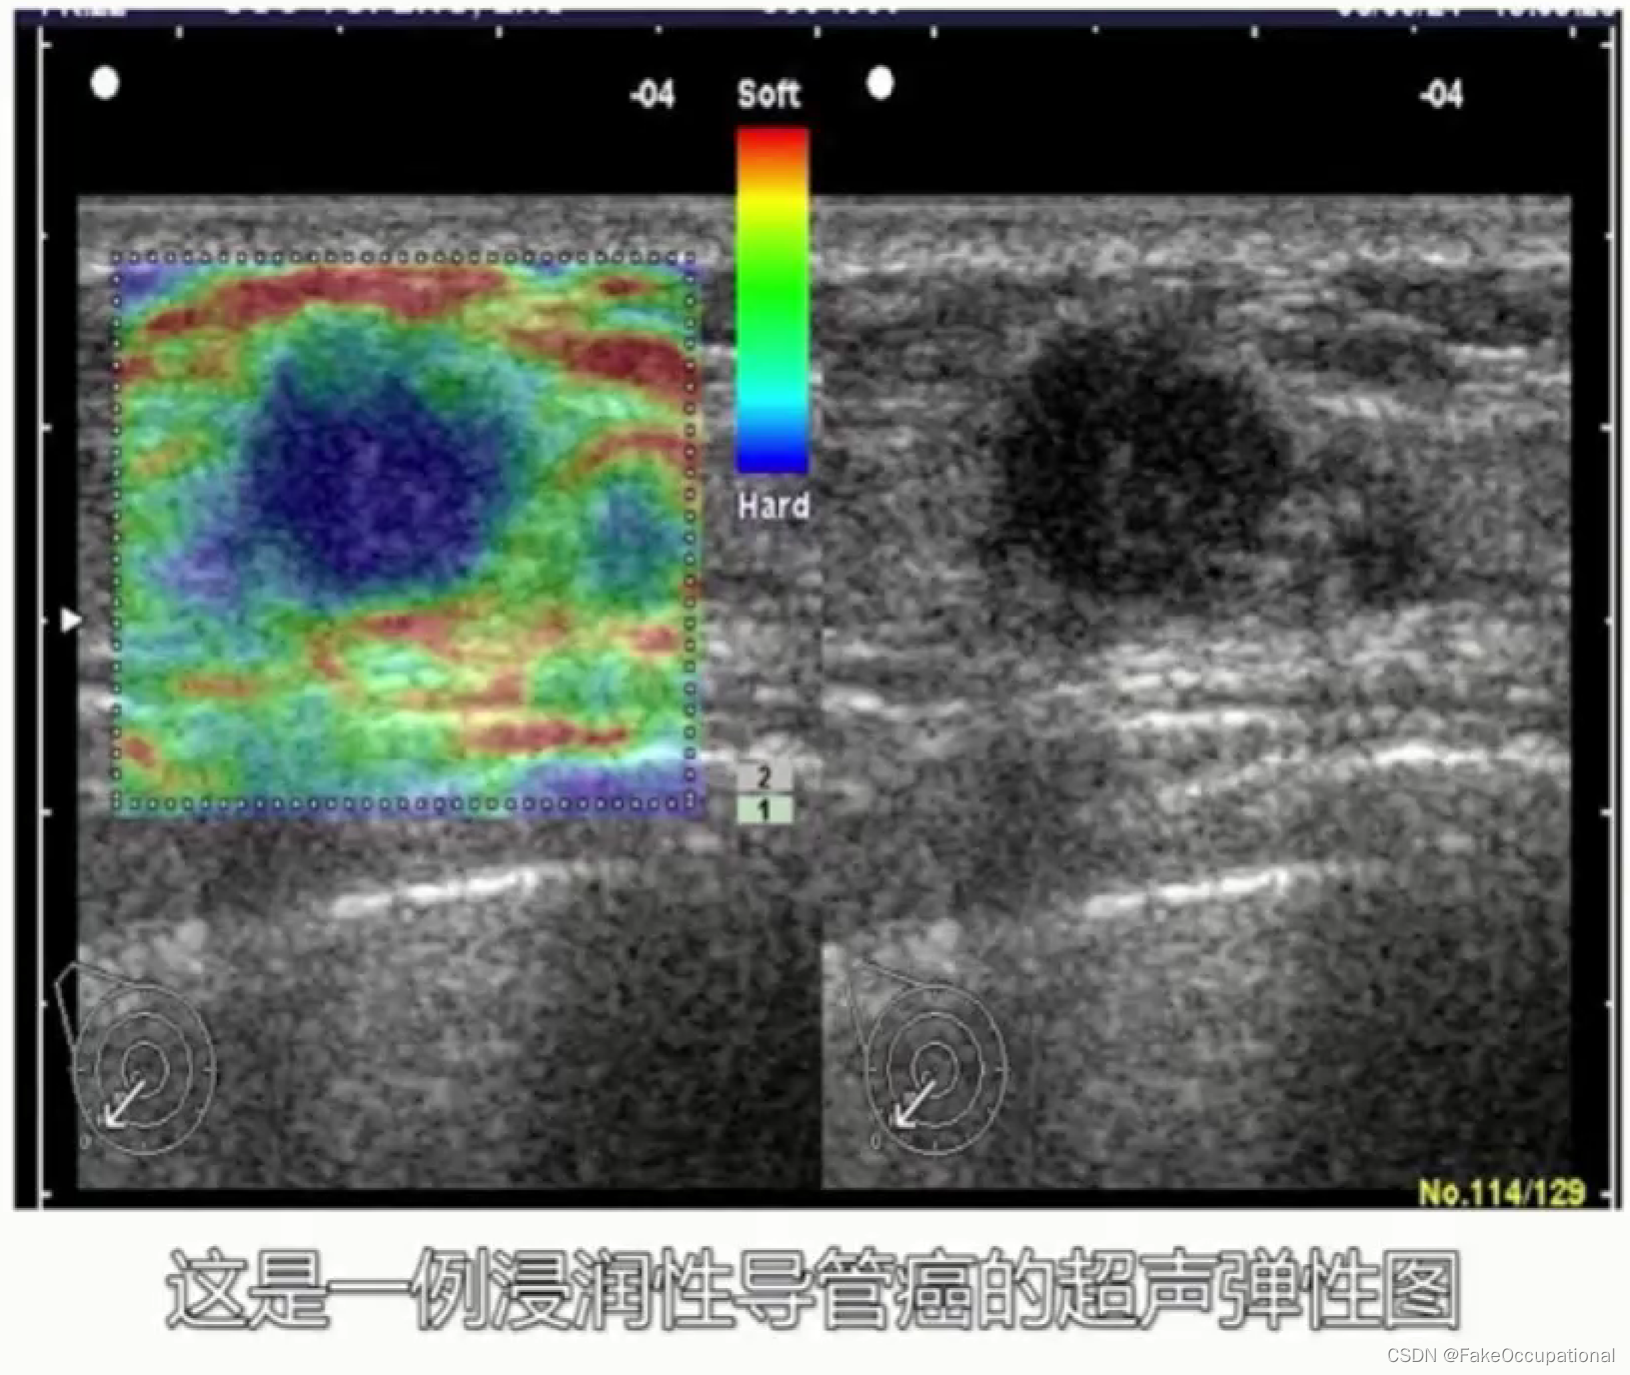

超声特殊检查与新技术

超声新技术

3.弹性成像

乳腺癌

- 其理论依据是恶性肿瘤常星离心性生长

乳腺超声进展

- 前者以彩色编码不同组织的弹性大小,